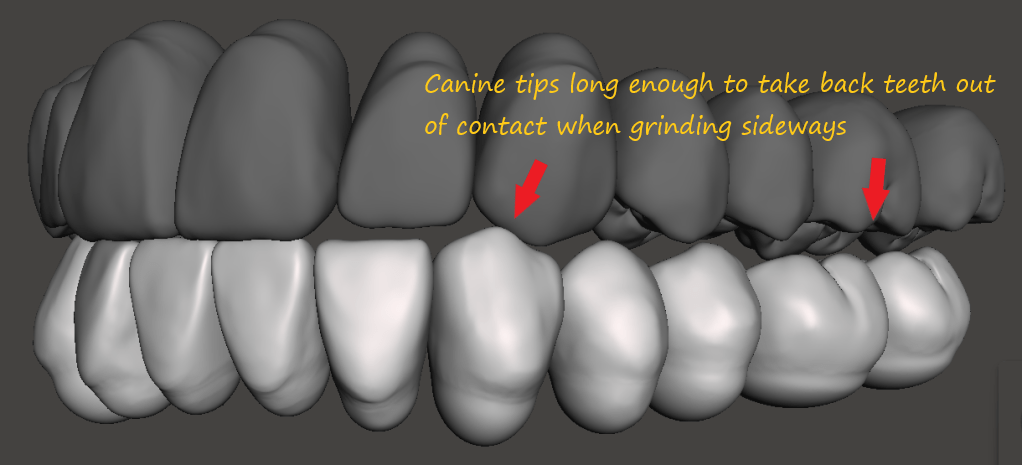

Prominent anterior teeth are desirable. It protect your back teeth from breaking each other when BRUXING– Its the concept of Canine Disclusion

Anterior Guidance or Canine Guidance

The form or shape of your front teeth are necessary to protect your back teeth when you grind or gnash your teeth (ie Brux). Front teeth are long skinny teeth usually with a single root, designed to tear food. Their length serve to transmit through the bone of your skull or your jaw that the food is perhaps too hard to tear so you stop. However if you really need to crack open that crab claw or pistachio nut you would use your back teeth.

Ideal Occlusion

The ideal shape of the front teeth is with centrals longer than the laterals and the canines are at the same level as the centrals. This will will give you a positive smile line

Without CANINE DISCLUSION back teeth will eventually get damaged when you grind your teeth sideways